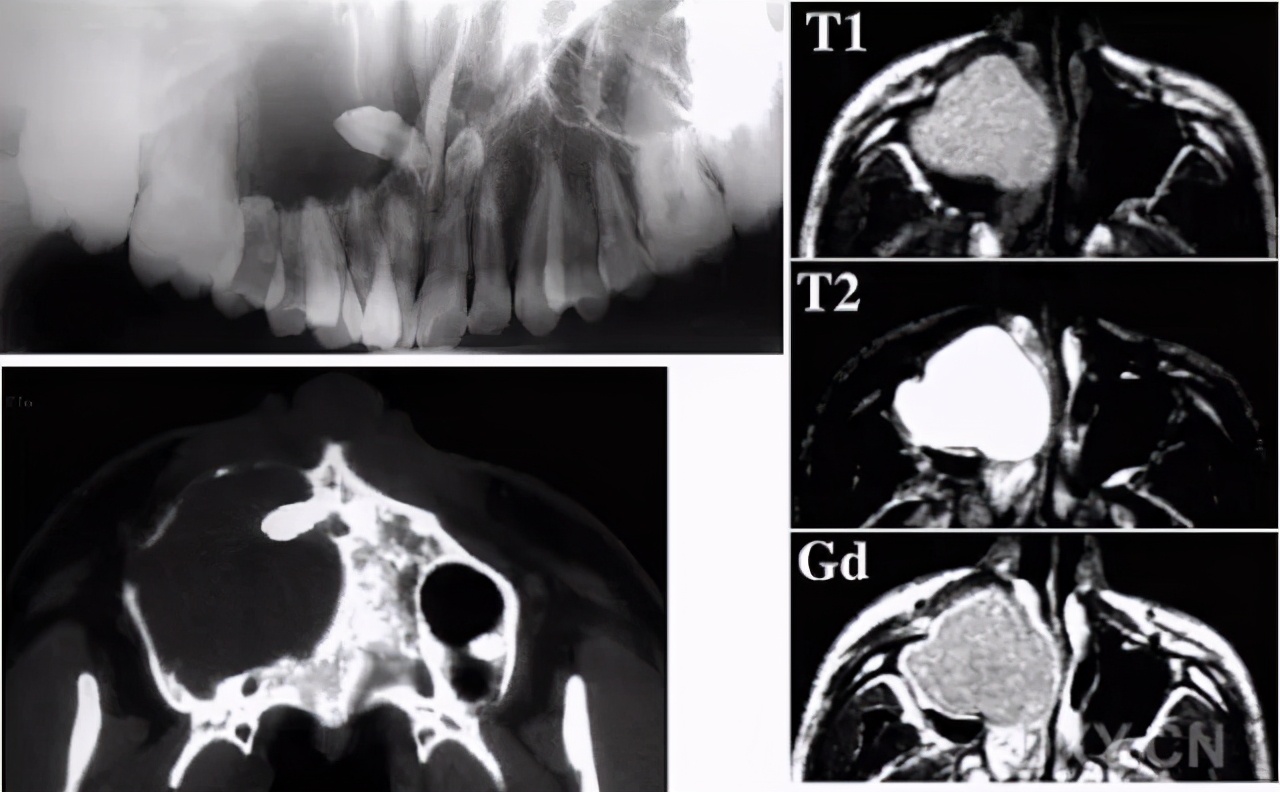

就上周吧,老朱在陕西都市快报上看到一则新闻,六十多岁的老刘从三年前开始就觉得自己的脸颊就有隐隐的胀痛却没注意,直到最近疼痛愈加明显,才赶紧去到口腔科检查。这一查不得了,拍片之后发现其实上颌窦里长了一个囊肿,而这囊肿里,竟有一颗异位的牙齿——原来,老刘得了鼻窦含牙囊肿。

老刘的囊肿已经有点严重了,脸的两侧出现了不协调,上颌骨被破坏,一侧牙齿也快脱落完了,如果病情再严重些还会造成面部塌陷畸形。最后,医生通过微创手术帮助老刘拿出了鼻窦里的牙齿,老刘也顺利出院。

鼻窦囊肿是指那些原发于鼻窦或者来源于牙或牙根并向上颌窦内发展的囊性肿物,一般属于耳鼻喉科。有朋友说,朱医生你不是口腔科吗,对这也有研究?那可不,毕竟容易挂错科。今天我们要聊的是上颌窦牙源性囊肿,这种囊肿一般是有上排牙发育障碍或者产生了病变导致的,牙齿突入上颌窦内变成了囊肿。像上文提到的老刘,主要是因为曾遭遇过外伤。

牙源性囊肿可以分为含牙囊肿,也就是老刘那种,一般在中青年之间产生的比较多,所含牙为未萌出的恒牙或额外牙。停留在牙槽骨中的未萌出恒牙可刺激造釉细胞,使呈增殖性变并产生分泌物而形成囊肿。牙釉质被包围在囊内,囊肿包膜为纤维组织构成,内膜为鳞状上皮。囊腔内含黄色或棕色液体;还有牙根囊肿,通常好发于老年人,为牙根感染,牙髓坏死,由牙根尖肉芽肿退行性变形成,他们都需要摘除囊肿然后处理病牙。比如老刘掉的半口牙,还得是让牙医给他再种上。